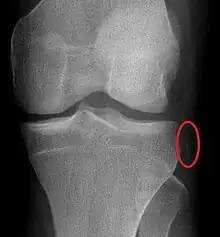

| Segond fracture of left knee | |

The Segond fracture is a type of avulsion fracture (soft tissue structures pulling off fragments of their bony attachment) from the lateral tibial plateau of the knee, immediately below the articular surface of the tibia (see photo).

Segond and reverse Segond fractures are characterized by a small avulsion,[5] or "chip", fragment of characteristic size that is best seen on plain radiography in the anterior-posterior plane. The avulsed fragment of bone may be very difficult to see on the plain x-ray exam, and may be better seen on computed tomography. MRI may be useful for visualization of the associated bone marrow edema of the underlying tibial plateau on fat-saturated T2W and STIR images, as well as the associated findings of ligamentous and/or meniscal injury.